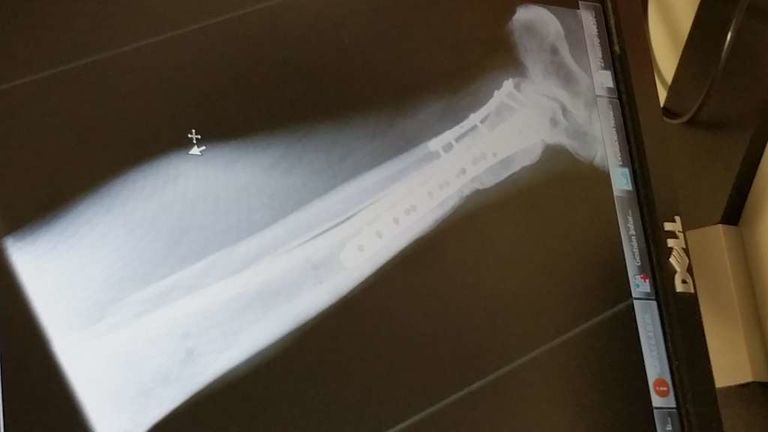

jerolo Publicado 17 de Marzo del 2016 Autor Compartir Publicado 17 de Marzo del 2016 Bueno,al fin consolidó,2 años y medio llorando_ me quedo más cojo de lo que pensaba,pues me tendrè que joder, no me queda otra,aùn ando con el puto bastòn....ahi van las placas Enlace al comentario Compartir en otros sitios web More sharing options...

jerolo Publicado 30 de Mayo del 2016 Autor Compartir Publicado 30 de Mayo del 2016 Ya no sé si tomarlo de coña o suIcidarme.....me fuí a urgencias porque no aguantaba el puto dolor y......6ª OPERACIÓN!!!!!!!!!!! para retirar las placas,o sea muletas otra vez y ahora que viene el veranito moto en el garaje,de puta madre.Por cierto,llevo 2 AÑOS y 8 MESES.espero que no le pase a nadie lo mismo Enlace al comentario Compartir en otros sitios web More sharing options...

jerolo Publicado 17 de Julio del 2016 Autor Compartir Publicado 17 de Julio del 2016 ¿Cómo va lo tuyo, Gerardo?? Ahora puedo decir que sí que estoy mejorando,me opera por 6°vez me sacaron las placas y mejoró rápido,aún ando con bastón pero en breve lo dejaré pero me quedo cojo;en septiembre 3AÑOS!!!!!no le deso a nadie que le pase lo mismo. Gracias por tu interés amigo trato_hecho Enlace al comentario Compartir en otros sitios web More sharing options...